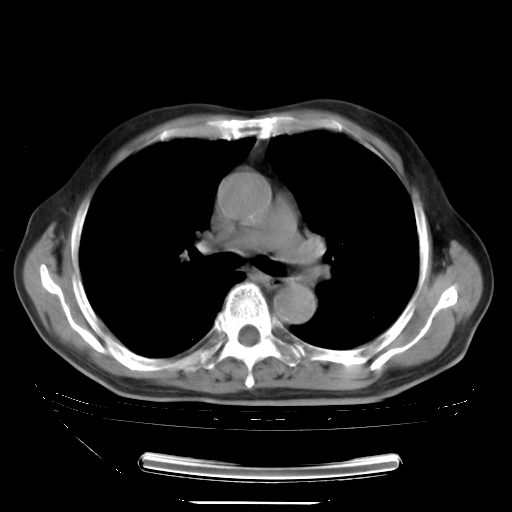

今天复查肺部CT,发现双肺广泛磨玻璃样改变。所以我把3月19日和5月9日相隔50天的肺部CT上传。请大家会诊。

5月9日肺部CT(在4月27日齐鲁医院肺部CT描述部分肺组织磨玻璃样改变,12天后肺组织广泛磨玻璃样改变)

2009年5月9日肺部CT

大致读了系列胸部CT:纵隔窗无明显异常,肺窗:从4、27至今:主要是双肺中下野外带可见毛玻璃样改变,目前处于急性肺泡炎阶段,至于原因考虑1、结替组织或胶原血管性疾病所致?2、恶性疾病如恶组在肺部所致的表现或细支气管肺泡癌?3、药物或其它原因如肺蛋白沉着症所致肺泡炎目前不太可能?总之,明天就去请我院的呼吸科、感染科、血液科和临免专家会诊哈。